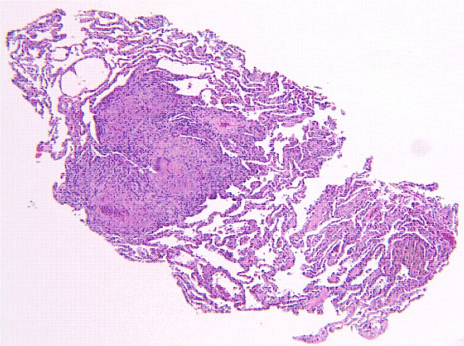

Pathology: The patient underwent flexible bronchoscopy and several transbronchial biopsies were taken. The biopsy sections showed alveolar parenchyma with small non-necrotizing granulomas (Figure 3). These granulomas tended to aggregate, as seen in Figure 3, with several nodules coalescing into a larger, rather discrete lesion. Also, there was minimal chronic inflammation around the granulomas and no inflammation extending out from the granulomas into surrounding lung parenchyma. These secondary features were useful in separating the granulomas of sarcoidosis from those associated with infections (where in addition, necrosis is commonly present). The granulomas of sarcoidosis typically have associated hyaline sclerosis (not evident here), but this finding was not a prerequisite for the diagnosis. At a higher magnification (Figure 4) several multinucleated giant cells were observed, another nonspecific feature. Sometimes distinctive inclusions can be seen in the granulomas of sarcoidosis (Schaumann bodies, asteroid bodies), but these are not specific for sarcoidosis. Whenever granulomas are present in a lung biopsy, the differential diagnosis is broad and includes infection, sarcoidosis, berylliosis, hypersensitivity reactions, pneumoconioses, certain lymphoproliferative diseases, aspiration, and even intravenous drug abuse. At a minimum, special stains for acid-fast organisms and fungi should always be performed.